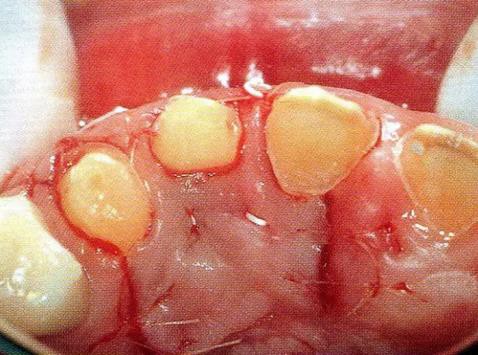

▼圖14-3 注射了EMD促生長因子后的狀態(tài)。